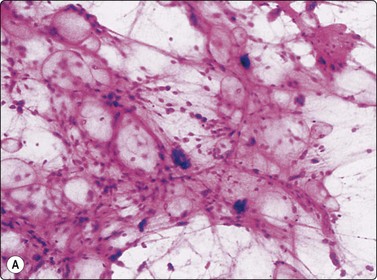

Lipoma is the commonest of all benign soft tissue tumors. Lipoma cannot be distinguished from normal adipose tissue cytologically – smears of both consist mainly of fragments of mature adipose tissue, a few single fat cells and fat droplets. The fat cells are large and have abundant empty cytoplasm and a small eccentric dark nucleus. A few strands of branching capillary vessels may be seen in the tissue fragments. It is important to make sure that the sample is representative of the suspected tumor. A needle with trocar is recommended for deep-seated tumors to avoid contamination with normal subcutaneous fat. In infiltrating intramuscular lipoma, the fragments of adipose tissue are intimately associated with muscle fibers. Skeletal muscle fibers appear in smears as large strap-like structures which are strongly eosinophilic (navy-blue in MGG) and have rows of small ovoid and elongated, pale nuclei. Cross-striation is often evident. The best indication of an infiltrating intramuscular lipoma is the presence of regenerating muscle fibers, since subcutaneous lipoma may be contaminated with skeletal muscle fibers if needling is too deep and traverses the tumor. The vascularity of an angiolipoma can often be appreciated in FNB smears (Fig. 15.19). Clinically, angiolipomas are often small, multiple and tender on palpation.

image

Fig. 15.19 Angiolipoma

Mature adipose tissue with anastomosing capillaries (MGG, LP).